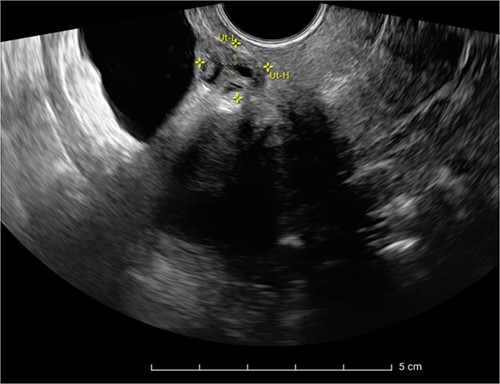

Expert transvaginal ultrasound scan was performed after referral with a CT scan to our tertiary center (Fig. 1). A 1.5–2 cm intramural endometriosis nodule was seen in the posterior bladder wall, not reaching the bladder mucosa (Fig. 2). On ultrasound scan, there was also evidence of adenomyosis of the uterus.

Ultrasound scan showing a heterogeneous endometriosis nodule in the posterior bladder wall not reaching the bladder mucosa.